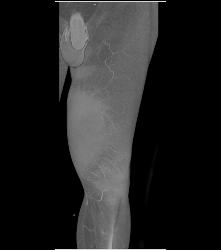

Thigh Hematoma Without Vascular Injury S/p Trauma